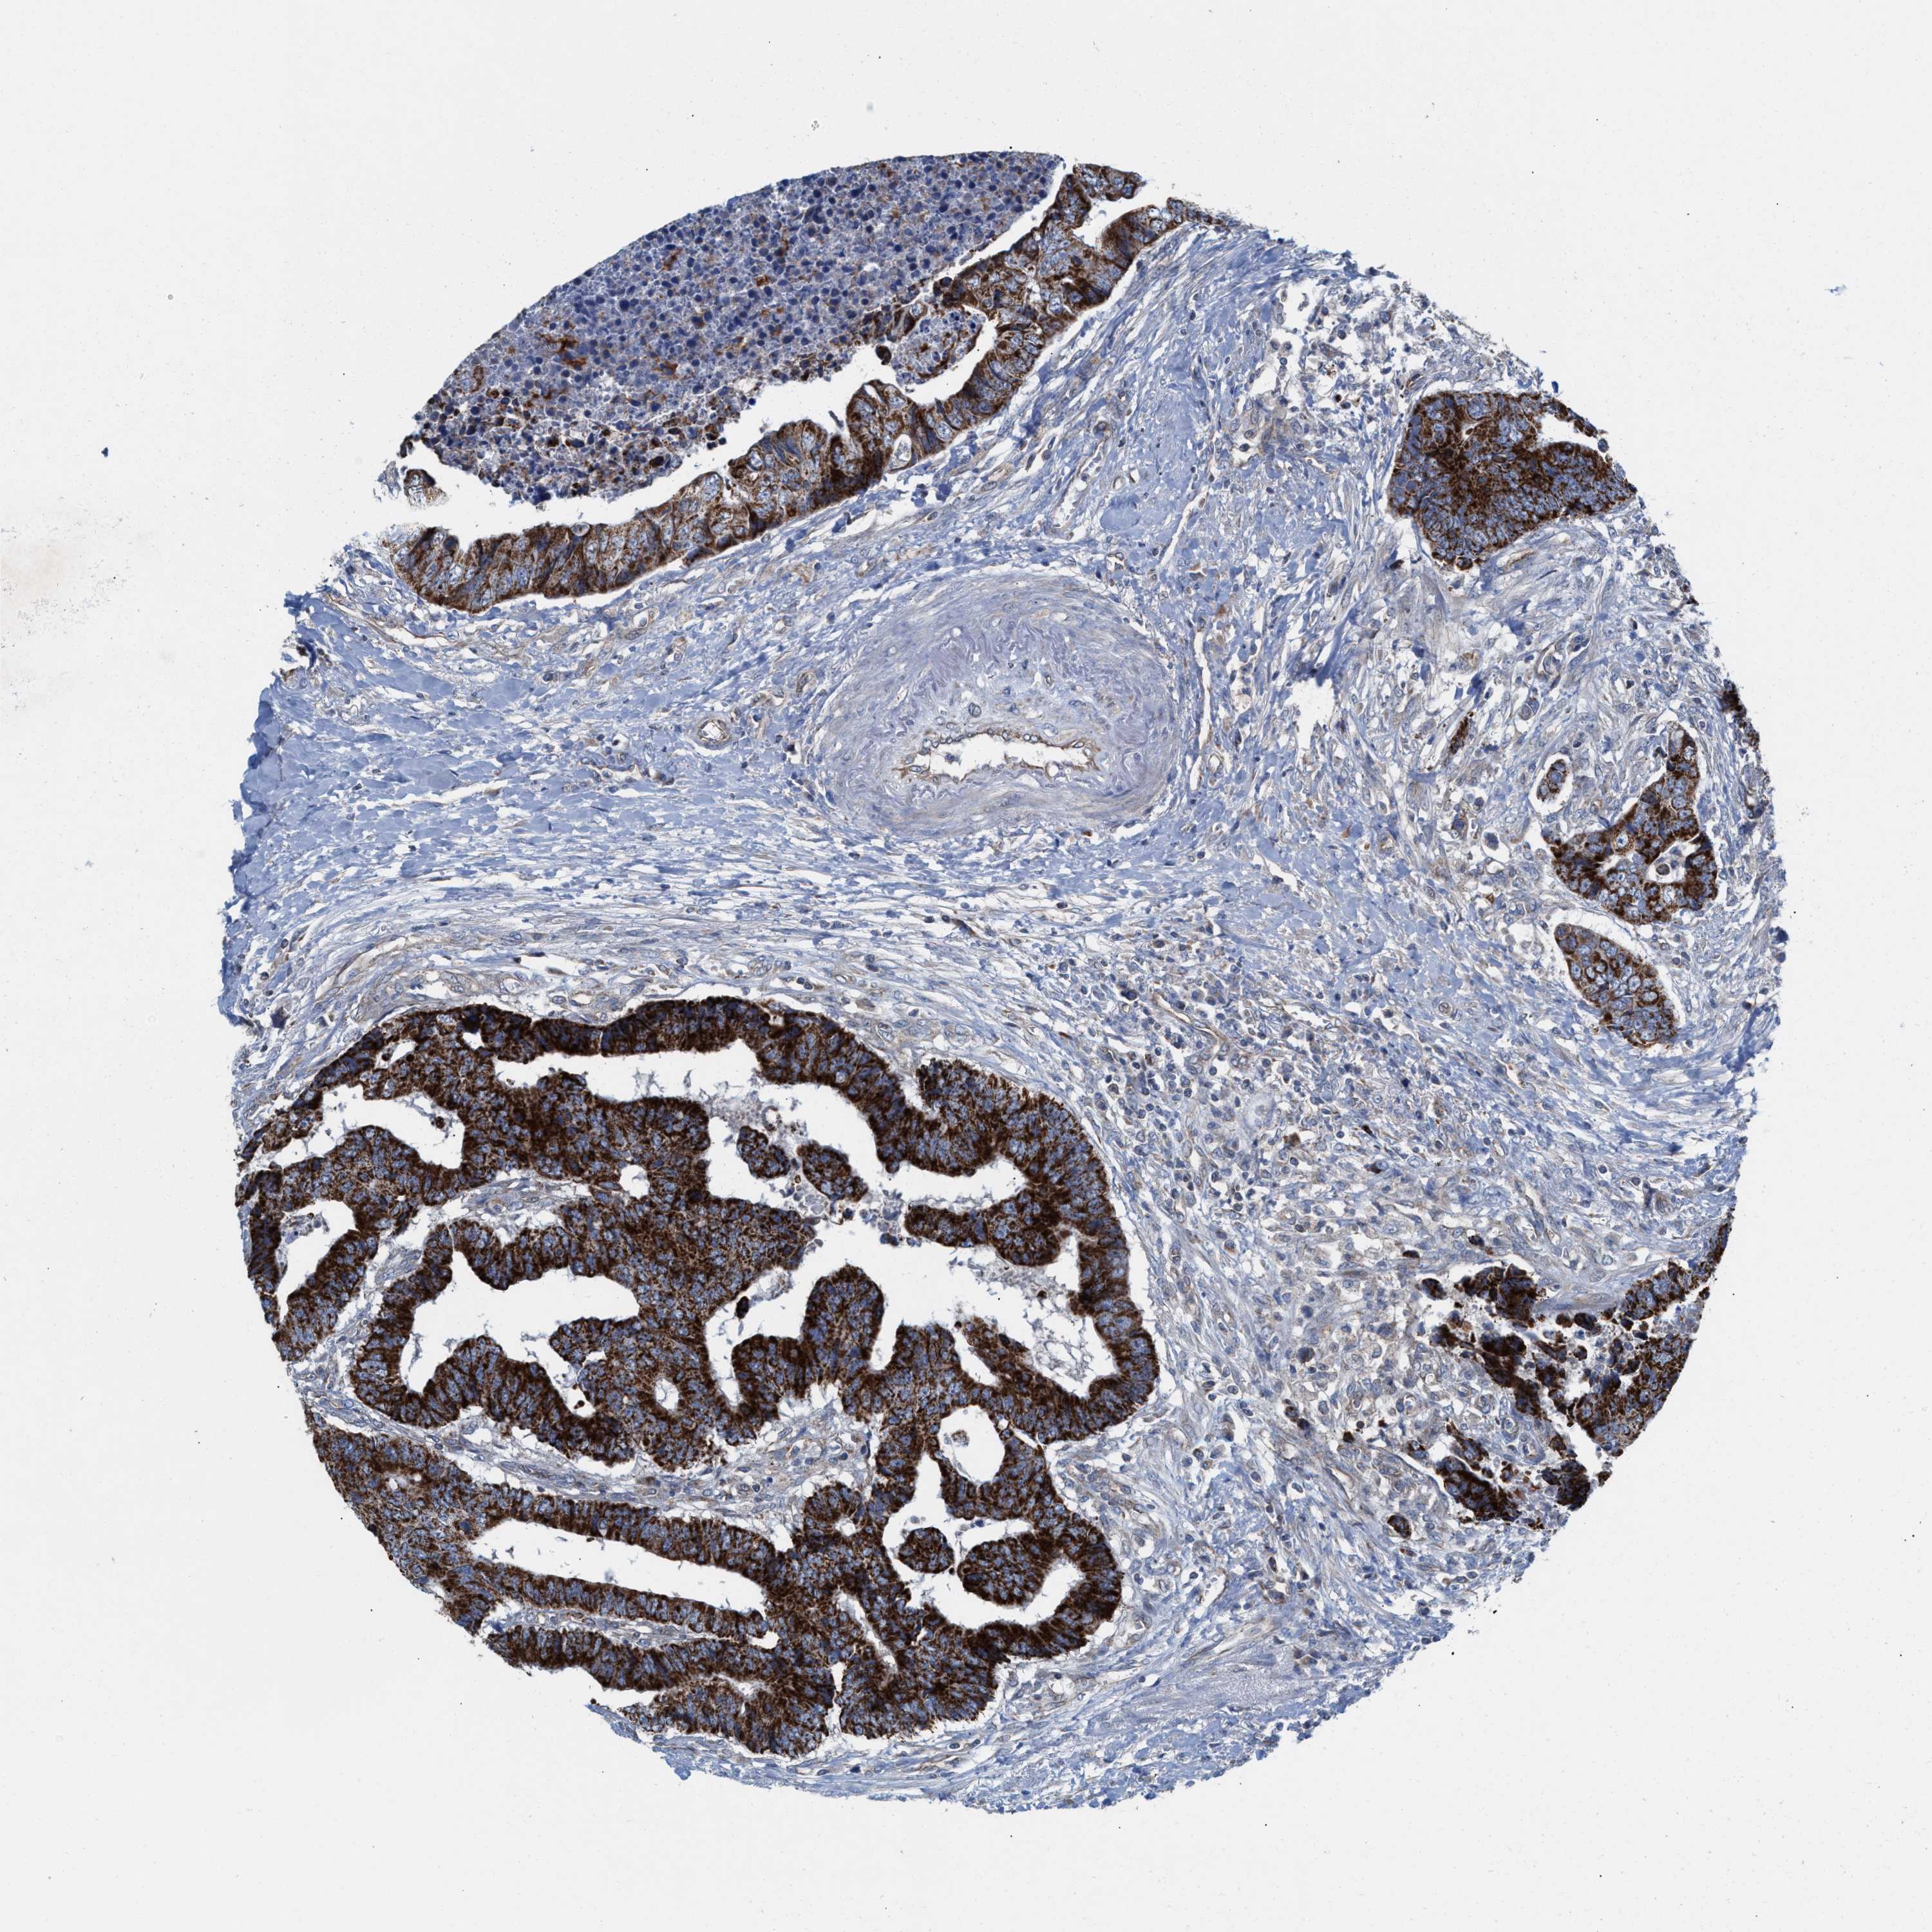

CANCER COLORECTAL CANCER Show tissue menu

Colorectal cancer

Human cancer

Colon adenocarcinoma